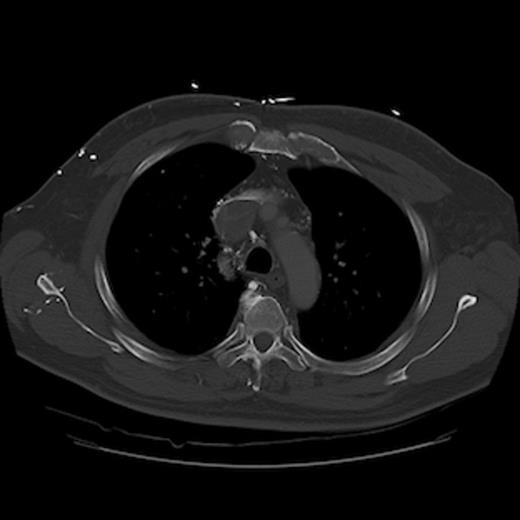

A 67-year old gentleman presented with progressive head and neck swelling and discomfort for several months. His symptoms were pronounced by bending over or straining in the bathroom. His symptoms worsened and he was referred for thoracic surgery consultation after a mass was seen on chest x-ray. He was diagnosed with SVC syndrome secondary to a mediastinal mass, demonstrated best by computed tomography (CT) [Figures 1, 2, 3].

CT of the chest (axial section) with intravenous contrast: demonstrates complete obstruction of the superior vena cava with a large intramural thrombus